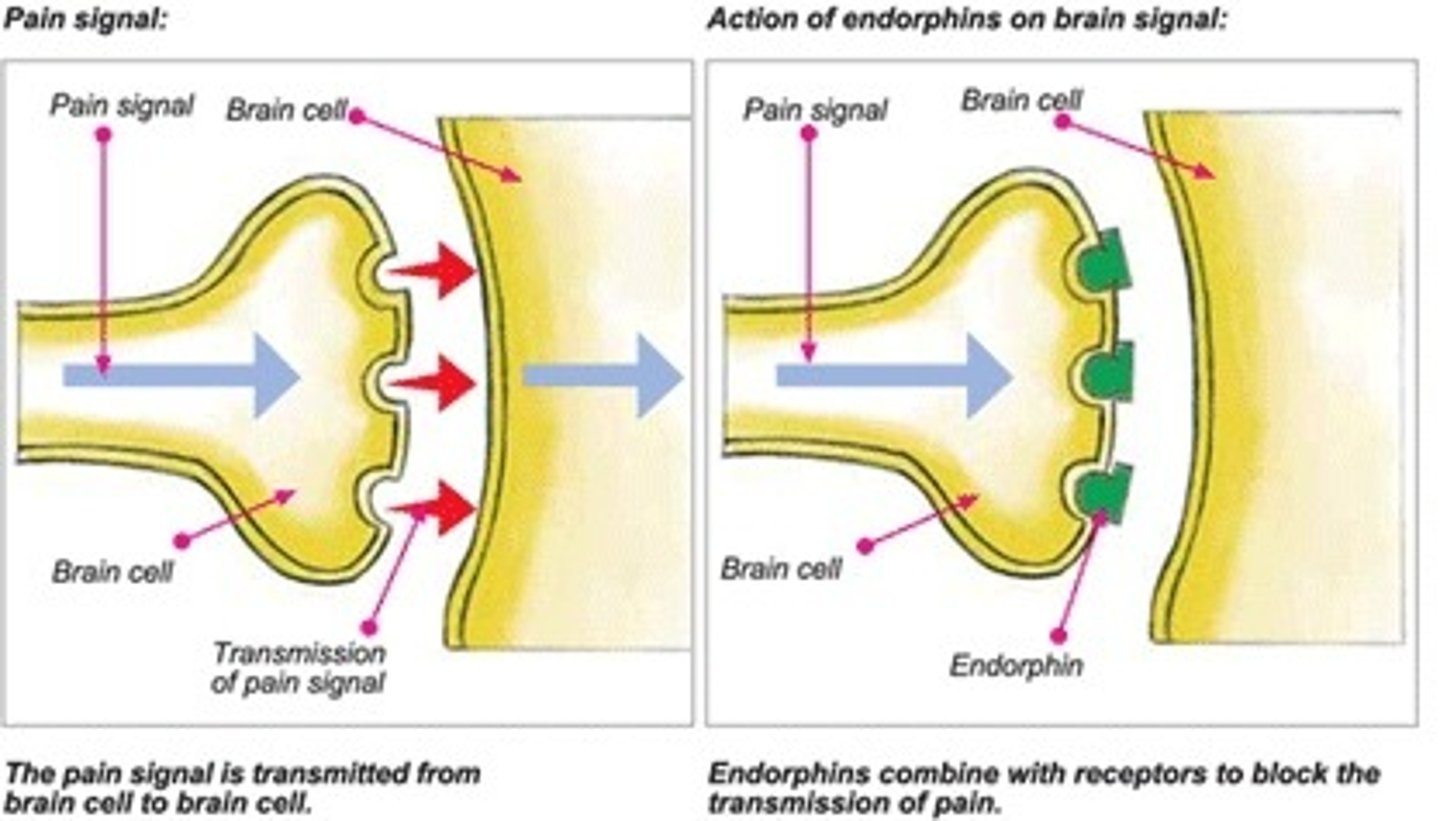

Endorphins

natural, opiate-like neurotransmitters that help manage pain, pleasure, stress, mood

bind to receptors and block a neurotransmitter's functioning

Agonists

these mimic a neurotransmitter and stimulate an action (e.g., morphine mimics endorphins)

Substance p

a neurotransmitter that is involved in the transmission of pain messages to the brain